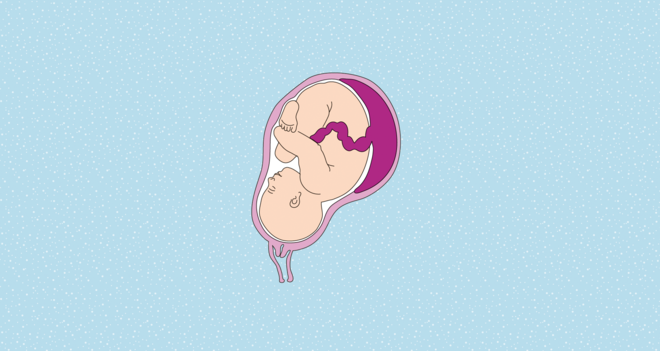

Wie sich ein Fehlsitz der Plazenta auf den weiteren Verlauf der Schwangerschaft und auch auf die Geburt auswirkt, hängt davon ab, wo genau die Plazenta in der Gebärmutter liegt. Zu unterscheiden sind:

- Placenta praevia totalis: Die Plazenta liegt direkt über dem Ausgang der Gebärmutter.

- Placenta praevia partialis: Der innere Muttermund ist teilweise vom Mutterkuchen überdeckt.

- Placenta praevia marginalis: Die Plazenta grenzt an den Rand des inneren Muttermundes.

Wo sitzt die Plazenta?

Die Lage des Mutterkuchens hat großen Einfluss darauf, ob ein Kind per Kaiserschnitt geholt werden muss. Je tiefer die Plazenta liegt, umso wahrscheinlicher ist der Eingriff